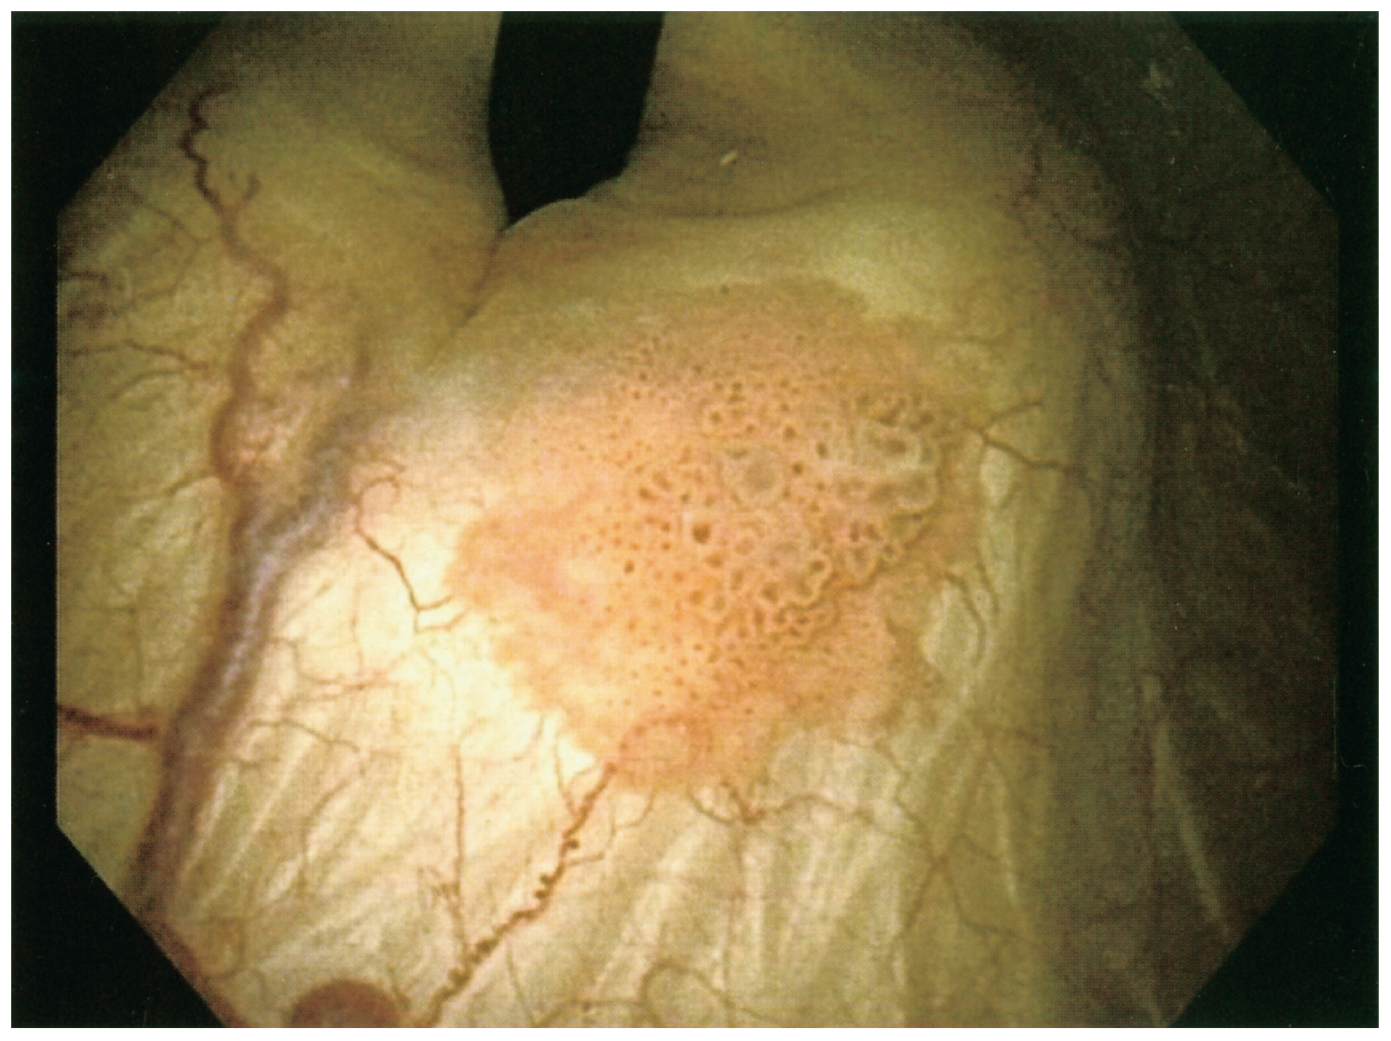

82歳の男性。定期的な泌尿器科検査のために来院した。2年前に,右尿管癌に対して腎尿管全摘除術を受けている。自覚症状はない。意識は清明。身長168cm,体重75kg。体温36.4℃。脈拍56/分,整。血圧110/56mmHg。呼吸数16/分。SpO2 98%(room air)。甲状腺と頸部リンパ節の腫大は認めない。腹部は平坦,軟で,肝・脾を触知しない。尿所見:蛋白(-),糖(-),ケトン体(-),潜血+,沈渣に赤血球10~19/HPF,白血球1~4/HPF,円柱を認めない。血液所見:赤血球432万,Hb 14.0g/dL,Ht 45%,白血球7,800,血小板31万。血液生化学所見:総蛋白8.3g/dL,アルブミン4.9g/dL,総ビリルビン0.7 mg/dL,AST 19U/L,ALT 12U/L,LD 137U/L(基準124~222),ALP 47U/L(基準38~113),CK 242U/L(基準59~248),尿素窒素35mg/dL,クレアチニン1.7mg/dL,血糖102mg/dL。膀胱鏡像を下に示す。胸腹部造影CTでは,遠隔転移は認めない。